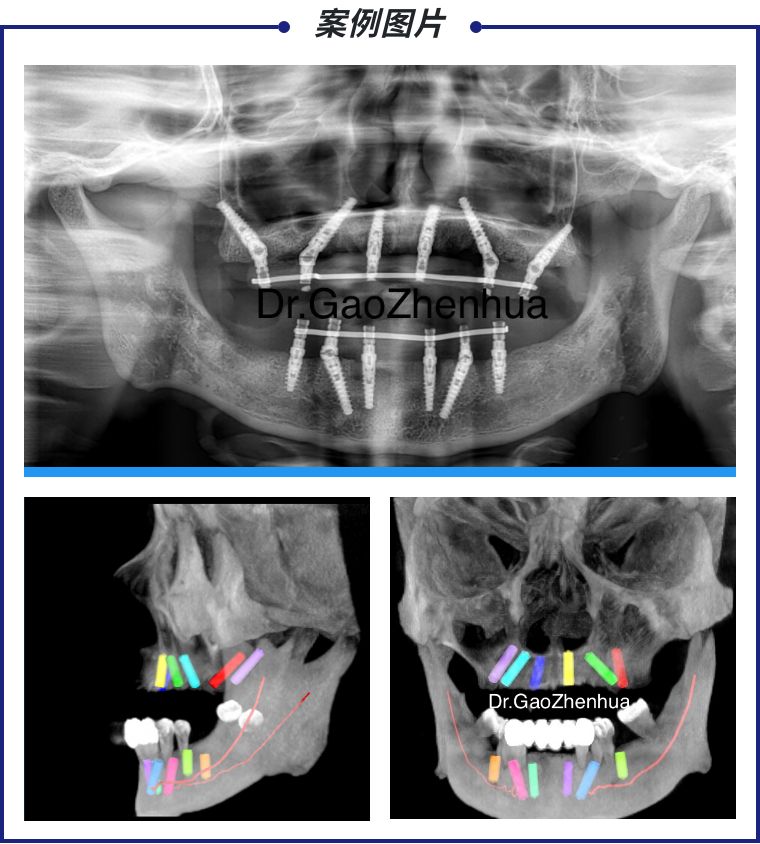

在对沈女士进行口腔检查后,高医生发现,许女士“上半口牙全部缺失,下半口牙不同程度的松动及重度牙周萎缩,下颌余牙骨也已经被吸收一部分”。仔细询问病史、口腔治疗史之后,结合许女士自身需求,高振华医生为沈女士制定了全口穿翼VIIV即刻负重整体解决方案,运用这个方案,许女士能够实现全口即刻重建,无需植骨,无需等待。

手术室里,高医生紧锣密鼓地操作,确定合位关系后,按常规局麻下,拔除下颌余留牙,切开,翻瓣,按种植位点逐级备孔,植入种植体,即刻印模转移,椅旁制作螺丝固位树脂增强整体桥,口内就位,调合,抛光;手术室外,许女士家属焦虑不安地等候,反复询问其他医护人员,亲人之间互相打气。